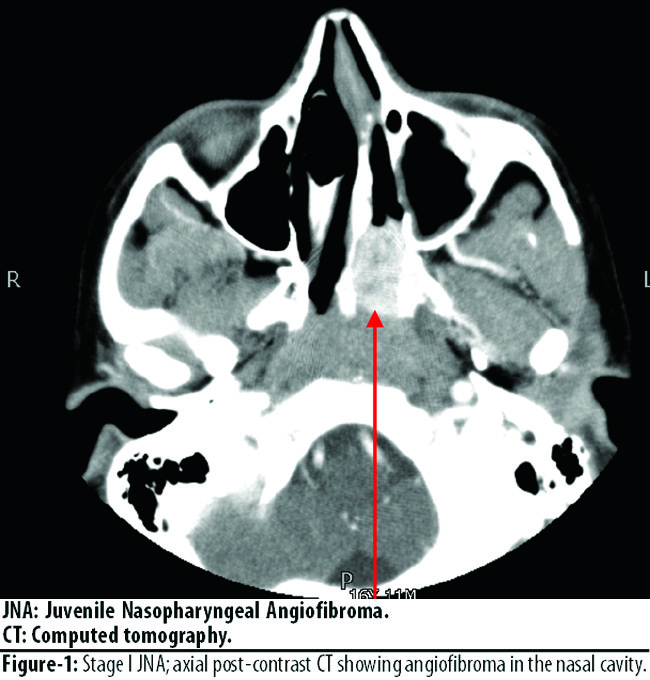

All patients were male, aged between 11 and 28 years with an average age of 16 5.6 years. According to the Andrews staging, 4 (22.22%) patients presented as stage I (Figure-1),

5 (27.77%) patients as stage II, 4 (22.22%) patients as stage IIIa (Figure-2),